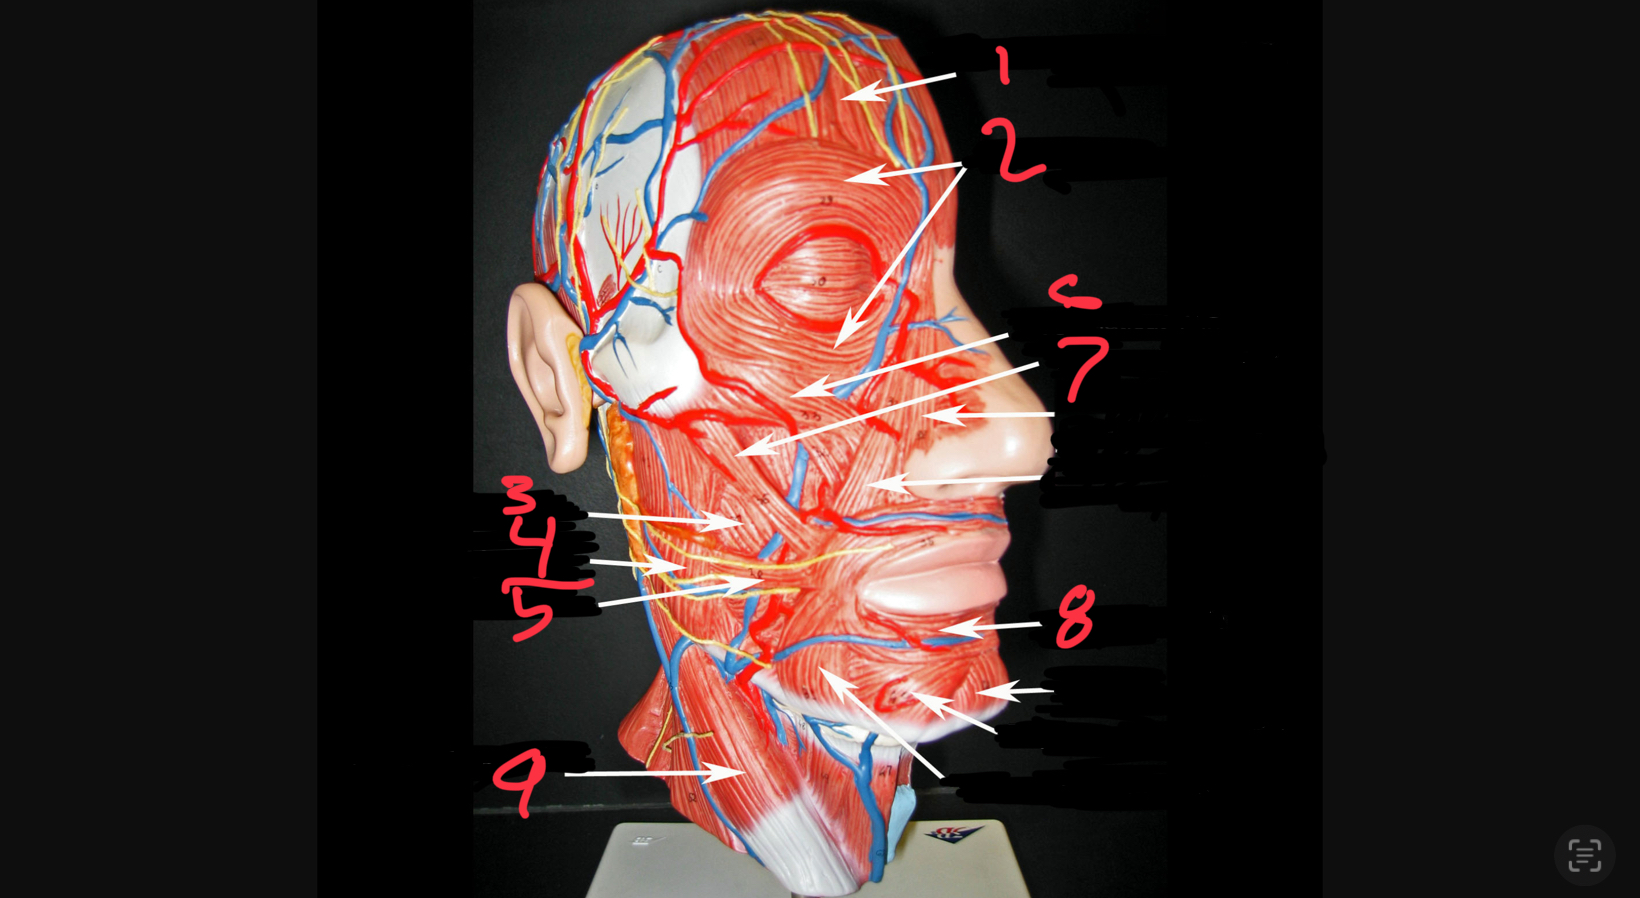

what #1

occipitofrontalis (frontal belly)

what is #2

orbicularis oculi

what is #3

buccinator

what is #4

masseter

what is #5

risorius

what is #6

zygomaticus minor

what is #7

zygomaticus major

what is #8

orbicularis oris

what is #9

sternocleidomastoid